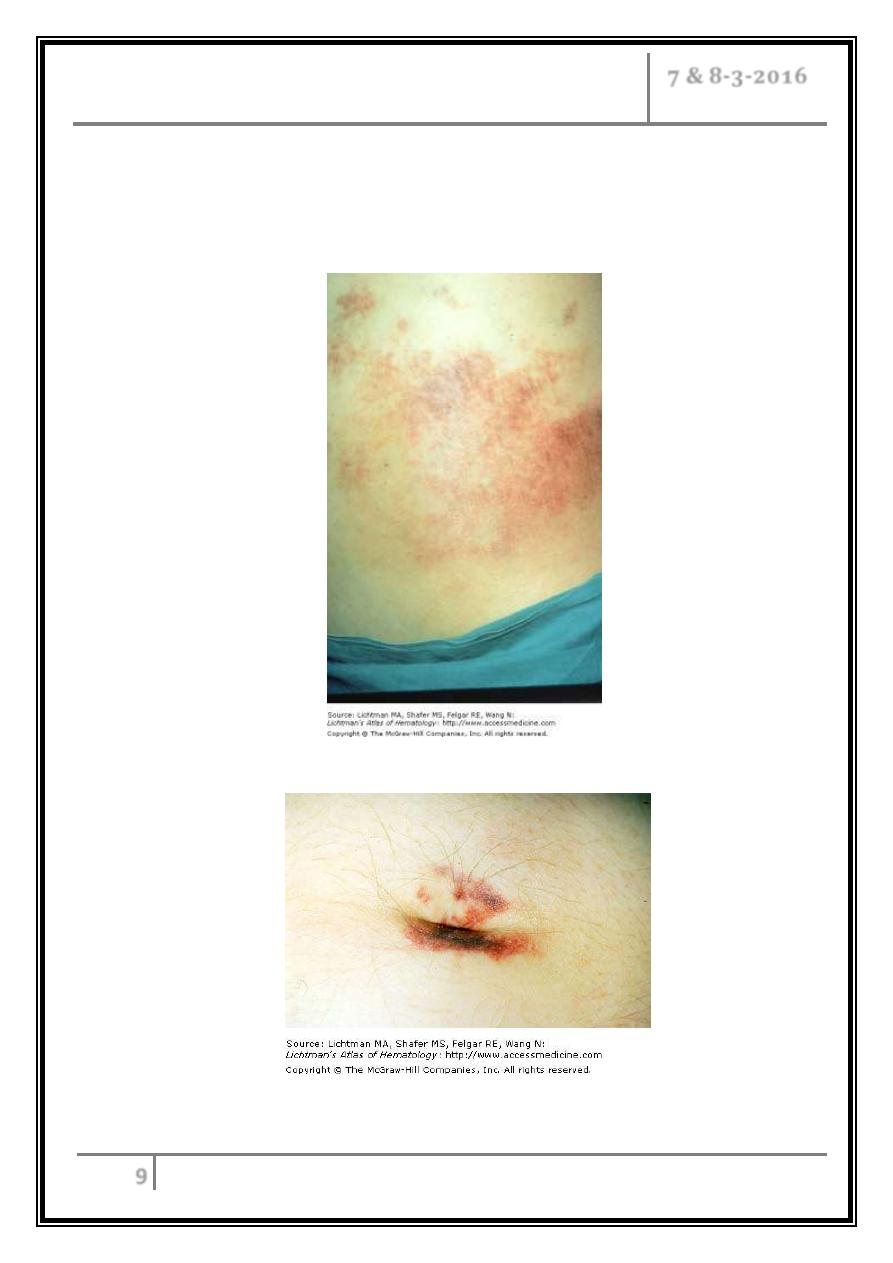

6- Discoloration of the flanks (Grey Turner’s sign) ,or periumbilical region

(Cullen’s sign) is a feature of severe pancreatitis with haemorrhage.

Grey-Turner

’s sign

Cullen

’s sign